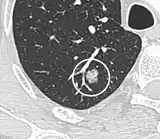

Lung nodule abutting a pulmonary cyst.[9]

• A lung nodule abutting a pulmonary cyst is a rare finding, yet indicating cancer.[9]